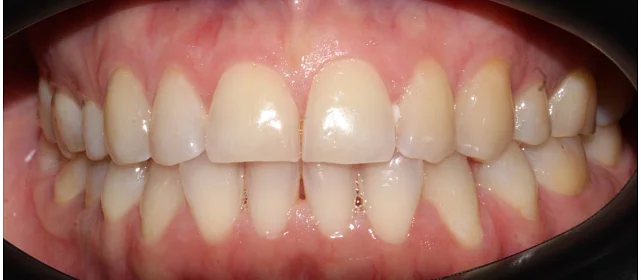

Зубы выровнены, смыкание нормализовано. Установлены несъёмные ретейнеры на обе челюсти, сняты сканы для ретенционных кап.

Решение: Поставили прозрачные элайнеры Click — начали с компактного набора из 20 кап. Основной комплект сделал основной объем работы, но для финальной доводки понадобился дополнительный набор из 10 кап. Итого 30 кап за 23 месяца. Результат — зубы на месте, смыкание в норме. Зафиксировали ретейнеры на обе челюсти, сняли сканы для ретенционных кап.